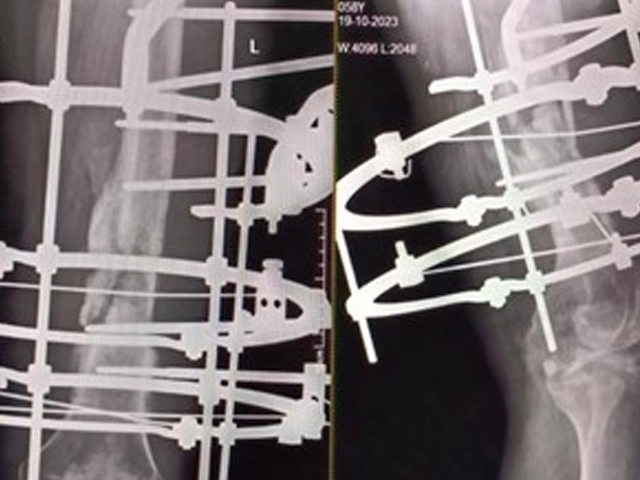

Trauma and Emergency Care:

The department operates a dedicated Level-I trauma center to manage accidents and emergencies. This facility provides prompt and effective treatment for patients with polytrauma, fractures, dislocations, and other musculoskeletal injuries. The trauma center is supported by an efficient Intensive Care Unit (ICU), anaesthetists, and Trauma Surgeons We also serve as a referral center for managing complications following trauma, such as infections, non-unions, and deformities.

Treatment of all routine, complex trauma and neglected trauma

5 OBSERVATIONAL STUDY ON MANAGEMENT OF OPEN TIBIA FRACTURES WITH LIMB RECONSTRUCTION SYSTEM (LRS) AS PRIMARY AND DEFINITIVE MODE OF FIXATION IN A RURAL BASED TERITIARY CARE CENTRE IN SOUTH INDIA